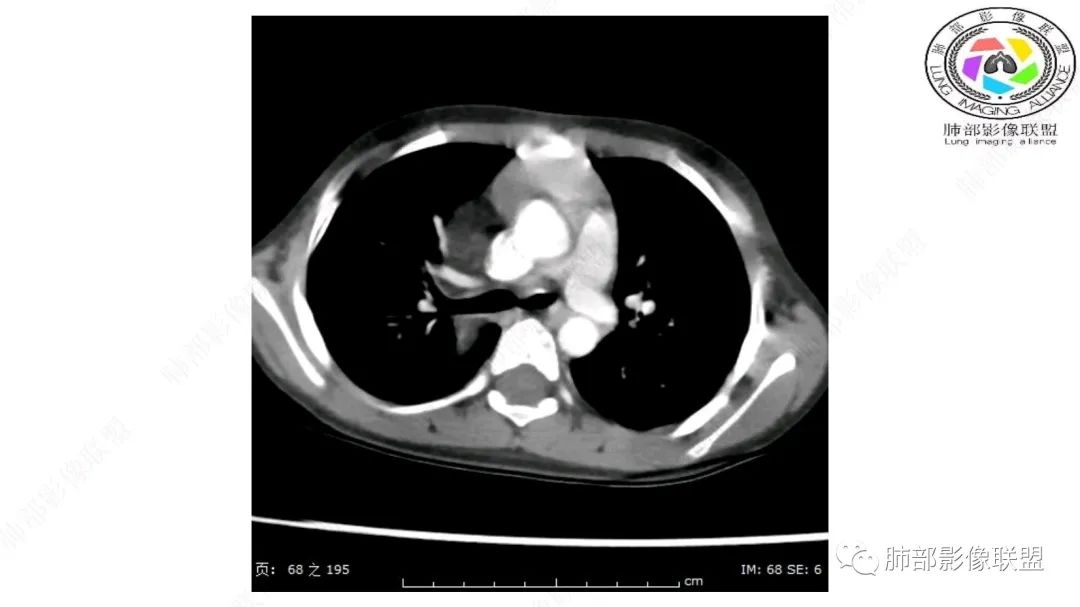

右上纵隔混杂密度肿块,边缘光整,与纵隔分界清,其内多发脂肪密度,增强无明显强化,其内血管穿行,考虑纵隔脂肪母细胞瘤,鉴别畸胎瘤,脂肪肉瘤。

右纵隔团状,密度不均,脂肪密度为主,内可见腺体样组织,类似乳腺,病灶边缘有分叶,与胸腺关系密切,增强后血管穿行。考虑胸腺脂肪瘤(不典型垂乳征),鉴别畸胎瘤。

三岁小儿,右侧纵隔巨大脂肪密度肿块,肺动脉穿行其中,密度欠均匀,未见明确实性成分,纵隔脂肪母细胞瘤,冬眠瘤鉴别纵隔脂肪增多症(多弥漫对称)。

患儿3岁 咳嗽检查发现纵隔占位。右肺上叶受压表现,占位以脂肪组织密度为主,似见分隔,首先考虑为脂肪母细胞瘤,鉴别脂肪瘤,畸胎瘤。

幼儿,右上纵隔团块状脂肪密度影,边缘清晰,内可见血管及支气管穿行,考虑脂肪瘤,鉴别畸胎瘤。

幼儿,右上纵膈团块,脂肪密度,内见分隔,增强病灶内见血管穿行,结合患者年龄,考虑脂肪母细胞瘤,鉴别脂肪瘤。

纵隔畸胎瘤,右前上纵隔团状脂肪密度?粘液样密度为主病变,病灶软边缘有分叶,内可见分隔,增强后血管穿行。3岁。考虑纵隔脂肪母细胞瘤,鉴别畸胎瘤。

定位肺外纵隔内,脂肪密度,内可见纤维分割,3岁,脂肪母,鉴别畸胎瘤。

右上纵膈混杂密度肿块,边缘光整,与纵膈分界清,其内多发脂肪密度,增强无明显强化,其内血管穿行,考虑纵膈脂肪母细胞瘤,鉴别畸胎瘤,脂肪肉瘤。

病灶属于交界区,主体位于肺内,占位效应明显,前方突入胸壁,胸腺受压变形,胸膜显示欠清楚;病灶包绕上叶肺动脉;似乎有体动脉供血。符合肺内的点:包绕上叶肺动脉分支;符合纵隔的点:前方似乎突入胸壁,与胸腺关系比较密切,但是与上腔静脉的关系提示病灶不支持纵隔来源,前纵隔的常规会将上腔静脉受压后移、外移,这是不符合的。

内部血管明显,部分病灶密度增高,单纯脂肪瘤不支持。可惜的是:没有提供CT值:是否强化?如果强化,警惕恶性;胸腺肯定不符合,胸腺会将上腔静脉朝后推移。

手术记录:见右肺上叶肿物,肿物与右肺上叶关系密切。与纵隔无粘连,逐步分离肿物,见肿物大小约6cm*5cm,边界清楚,于右肺上叶粘连,边界清楚,肿物包绕右肺上叶血管及支气管。超声刀逐步游离肿物,完整切除肿物,右肺上叶肺组织无破溃,表面无出血。

1.右上肺-纵隔交界区巨块影,主体位于右肺一侧,紧贴胸腺、头臂干、右锁骨下动脉、上腔静脉、奇静脉等,不能分离,但病灶整体边界清楚。注意上述相邻腔静脉等结构未见受压变形,纵隔亦未见明显向左推移,至少提示两点:

2.肺动脉穿行也许是肺内来源最重要支持点!

CT扫描对脂肪类肿瘤常有独到价值。肿块孤立、边界清楚,未见周围浸润,较均匀脂肪样低密度,高度提示为良性!

发生于成人为脂肪瘤表现,婴幼儿自然会想到脂肪母细胞瘤。两者生物学行为并无本质区别。

脂肪母细胞瘤由成熟程度不同的脂肪组织、纤维间隔、黏液基质、小血管丛等间质成分组成,以脂肪组织与黏液样基质为主,其影像学表现取决于上述组织成分。典型的CT和MRI表现为:前后纵隔均可发生,常见于前纵隔;肿块大小不一,直径多在3cm~7cm,密度均匀,CT值呈水样或脂肪密度,脂肪组织密度或信号为主的肿块,其内密度或信号不均匀,可见粗细不一的分隔影,且有结节、片状影,后者可呈轻中度强化;结节状肿瘤包膜完整;弥漫性者包膜不明显,常呈浸润性生长;周围结构为受压和推移改变,可有少量胸腔积液,淋巴结无增大。